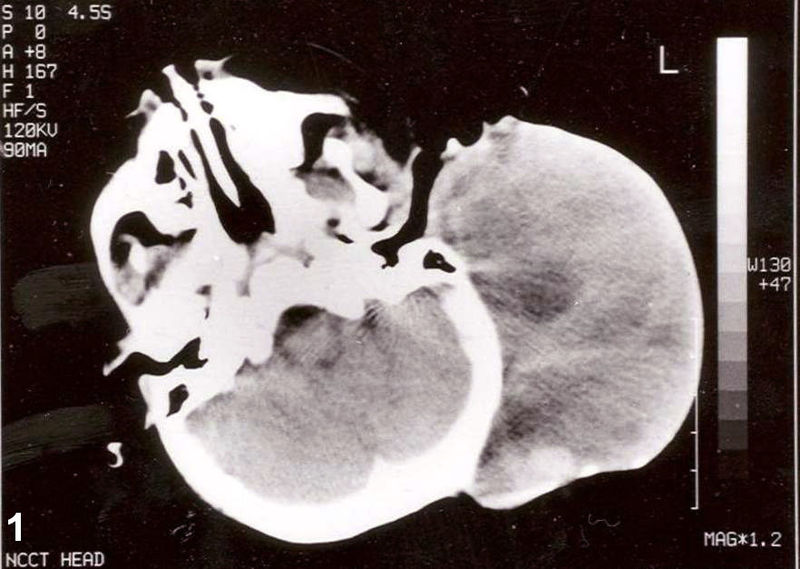

Rhabdomyomas can develop in heart muscle, termed cardiac rhabdomyomas, which are associated with tuberous sclerosis.

Although rhabdomyomas are uncommon in general, they are the most frequent kind of cardiac tumor among infants and young children.

Rhabdomyosarcoma